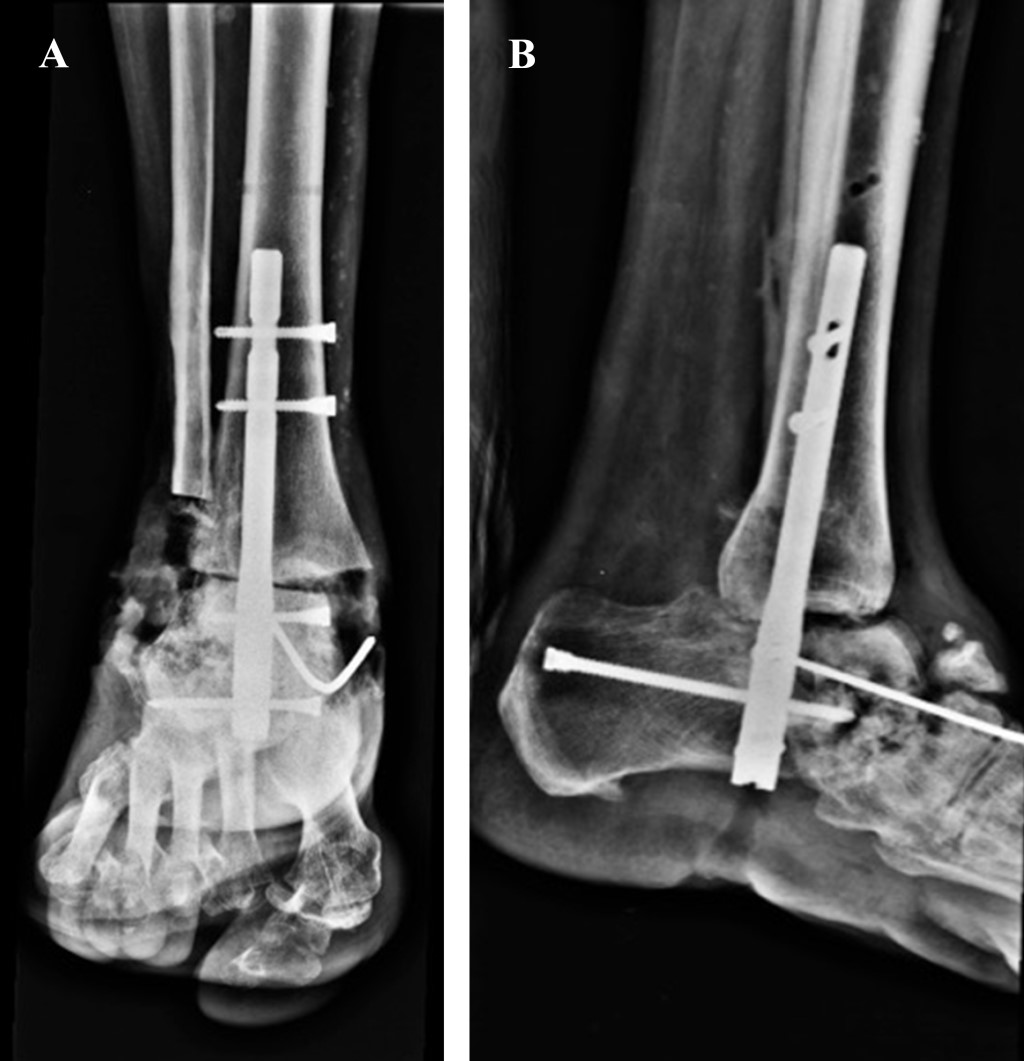

Las radiografías se consideran el método de diagnóstico más útil. Permite identificar el área de compromiso, evalúa la calidad ósea y si el proceso es agudo o crónico, el cual puede ser complementado con una tomografía axial computarizada (Figura 1).

Se analizaron 11 casos de pacientes con artropatía de Charcot tratados con clavo centromedular retrógrado (Figura 2) de los cuales ocho (72.7%) correspondieron al sexo femenino y tres (27.3%) al masculino. La edad mínima fue de 31 años y la máxima de 68 años con media de 53.2 ± 11.4 años.

Figura 1

Figura 2